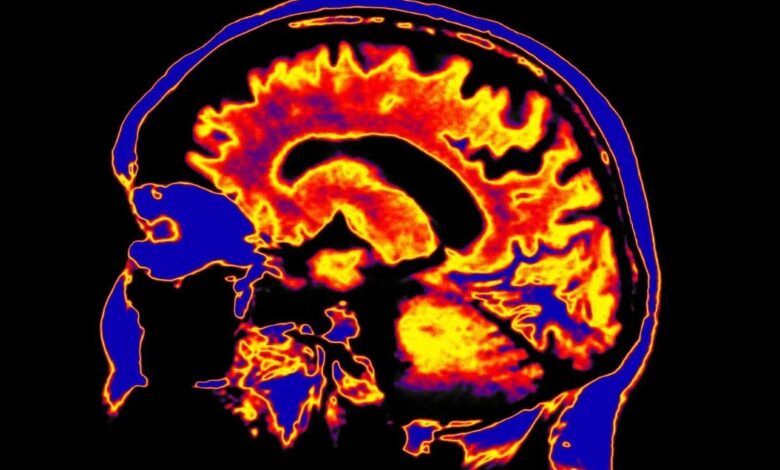

كل أسبوع تقريبًا تنشر دوريات علم الأعصاب والطب النفسي عشرات الدراسات التي تكشف اختلافات جديدة في الدماغ. مرة نجد اختلافًا في شبكات الاتصال العصبي، ومرة في طريقة معالجة المعلومات، ومرة…